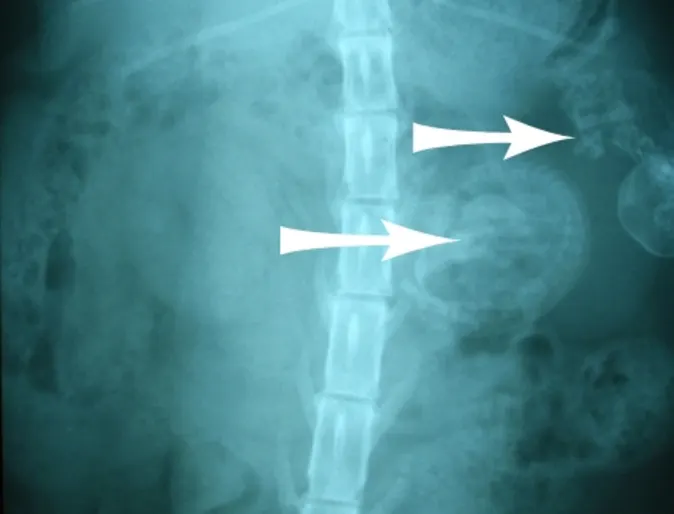

Enormous Tumor on a Spleen

Moses is a 8 year old Labrador Retriever who was slowly gaining weight for almost a year. Moses actually started appearing like a pregant dog before seeing us which is hard to do for male dog. He also started to become quite lethargic and he stopped eating.